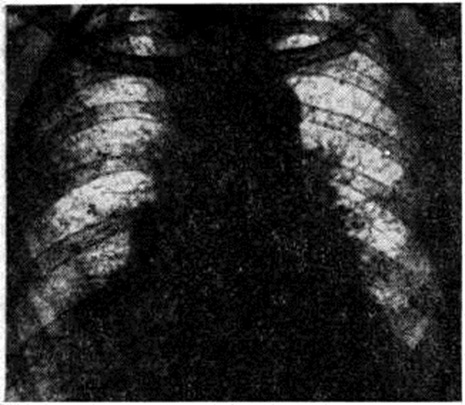

Диагноз устанавливают на основании характерных клинические, признаков. Среди дополнительных методов исследования важным является рентгенологический. Ранними рентгенологическое признаками Хаммена — Рича синдром являются усиление и деформация лёгочного рисунка, обычно выявляемые в нижних и средних отделах лёгочных полей. Прозрачность этих участков понижается за счёт появления множества тяжистых теней, идущих радиально от корней к периферии по ходу бронхов и сосудов. Характерен сетчатый, ячеистый рисунок, обусловленный разрастанием соединительной ткани вокруг долек и ацинусов (рисунок).

По мере прогрессирования процесса обмечается уплотнение теней корней и утолщение пристеночной, междолевой и диафрагмальной плевры; верхние отделы лёгких также постепенно вовлекаются в патологический процесс. На фоне усиленного и деформированного лёгочного рисунка появляются нечётко очерченные очаговые тени небольших и средних размеров, частично сливающиеся между собой. Подвижность диафрагмы уменьшается, реберно-диафрагмальные синусы частично, а затем полностью облитерируются.

При далеко зашедшем процессе в кортикальном слое лёгких по периферии лёгочных полей появляются кистовидные полости, диаметром до 2—3 сантиметров, некоторые с уровнем жидкости. Томография (смотри полный свод знаний) и бронхография (смотри полный свод знаний) позволяют иногда обнаружить цилиндрические, мешотчатые и смешанные бронхоэктазы, обычно в нижнемедиальных отделах лёгких. Характерным для течения Хаммена — Рича синдром является неуклонное нарастание отмеченных рентгенологическое изменений.